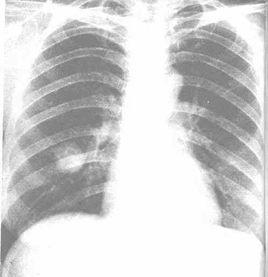

影像學表現

l.圓形、橢圓形、三角形或啞鈴形腫塊,邊緣多光滑銳利,密度中等偏高.直徑以3~6cm多見。周圍有時可見不規則條索影。

2.腫塊內可見空洞形成,偶有鈣化,多數密度均勻。

3.假性淋巴瘤型可見腫塊內支氣管氣相。

4.多為單發病變,少數可為多發。

5.動態追蹤觀察,腫物生長多較緩慢,腫物倍增時可長達十多年。